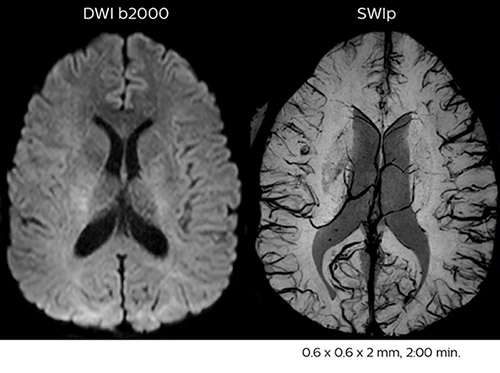

Fast acute stroke protocol

This is an example of acute ischemic stroke with distal occlusion of the right posterior cerebral artery. Note the improved visibility of the ischemic territory on the diffusion weighted image with high b-value. The 3D FLAIR shows a distal PCA occlusion. The fast SWIp depicts the thrombus on the isolated second echo image. The total scan time (including SmartBrain, preparations and a fast 3D T1w TSE Gd) is 8:00 minutes.

Acute right motor deficit and aphasia

In this patient with acute right motor deficit and aphasia, the b2000 diffusion weighted image is normal. The SWIp image demonstrates more prominent veins in the right hemisphere, which could reflect increased deoxyhemoglobin contents. Fast ASL shows low CBF regions in the left frontal lobe. A follow-up ASL after one hour demonstrates high CBF values in the same area. The final diagnosis was migraine with aura.

Improved diffusion imaging in stroke patients

Using MultiBand SENSE allowed the staff to improve their diffusion quality. “Our diffusion sequence was already fast before, about 40 seconds. Now with Elition, it still lasts 40 seconds, but we improved the spatial resolution by 0.2 mm and use high b-values to be more sensitive to visualize changes related to acute stroke,” says Dr. Savatovsky.

The ability to perform more sequences can help in making a swift and confident diagnosis. “For example, our stroke cases usually include the regular sequences that every center does (b1000 diffusion, FLAIR, time-of-flight angiography), but we also image supra aortic vessels, and we can replace a gradient echo sequence with a fast 50-second susceptibility-weighted sequence, and all of this doesn’t add much time. because all the regular sequences are accelerated on Elition.”

“The time savings with Compressed SENSE and MultiBand SENSE make it easier to add sequences to give us additional insights. Depending on the context and the first results, we might add a DSC perfusion to assess the ischemic penumbra, an ASL perfusion to help find an alternative cause in case of normal diffusion, or add a high-resolution T1 sequence for a stroke patient, to quickly assess wall imaging in emergency cases. The additional sequences can help improve patient management, because we can already consider some alternative diagnoses if the morphological MRI is normal.”